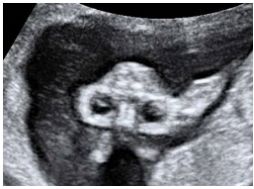

56.36歲孕婦,G5P2SA1AA1,妊娠16週,接受超音波檢查,結果如圖所示: 則胎兒異常器官名稱與特徵(sign)為何? (A)head,frog sign (B)cerebellum,banana sign (C)pons,lemon sign (D)ventricle,keyhole sign